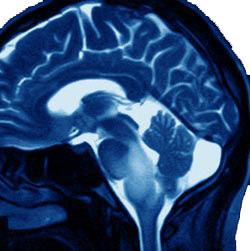

DBSG are considered to be one of the most difficult types of cancer to treat. It combines highly malignant characteristics with the very difficult location of the brainstem. DBSG are inoperable because they involve most of the brainstem (diffuse and intrinsic). The number of children in the U.S. with brainstem gliomas is approximately 660. Absent treatment, the survival rate from time of diagnosis is six months or less.